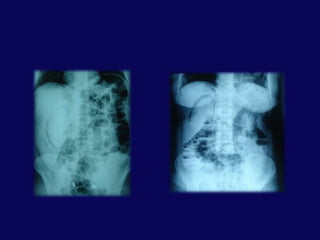

Gastrografin ile duodenumdan kaçak

BT- pankreas çevresi, retroperitoneal serbest hava, kontrast ekstravazasyonuTanıDÜZ GRAFİAlt torasik- Üst lombervertebra kırığı

Sağ psoas kası boyunca veya sağ böbrek hizasında hava